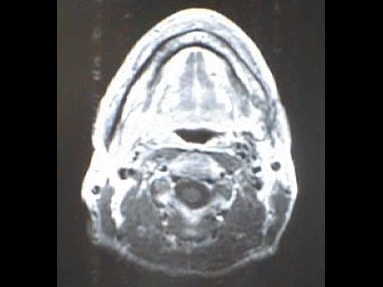

中咽頭末期がんMRI画像②

入院当時MRI画像②

中咽頭末期がん消滅時MRI画像②

入院3か月後癌消滅MRI画像②

中咽頭末期がんMRI画像③

入院当時MRI画像③

中咽頭末期がん消滅時MRI画像③

入院3か月後癌消滅MRI画像③